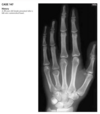

Anteroposterior view of the hands of a

patient with chronic renal failure shows subperi-

osteal resorption along the radial aspect of the

middle phalanges of the index and middle fingers

(Fig. 2.23.1, arrows). There are vascular clips from

a graft at the radial aspect of the right wrist (arrow-

heads). A lateral view of the skull in the same patient

(Fig. 2.23.2) shows a salt-and-pepper appearance.

Secondary hyperparathyroidism (HPT)

HPT is a general term referring to an

increased serum level of parathyroid hormone. Pri-

mary HPT results from an intrinsic abnormality in

the parathyroid gland (e.g., an adenoma, hyperpla-

sia, carcinoma). Secondary HPT is caused by a dif-

fuse, adenomatous hyperplasia, and tertiary HPT

develops from an autonomous parathyroid ade-

noma caused by the chronic overstimulation of hy-

perplastic glands in renal insufficiency.

Bone resorption along the radial aspect of

the middle phalanges of the hand (especially of the

second and third digits) is considered diagnostic of

this disorder.

Bone softening may lead to

basilar invagination, wedged vertebrae, bowing of long bones, and slipped capital femoral epiphyses.

Brown tumors, which are lytic, expansile lesions

that may mimic metastases or myeloma, occur in

the jaw, rib, and pelvis and are more commonly

seen in primary HPT. Osteosclerosis, more com-

monly seen in secondary HPT, is characterized by

bandlike sclerosis on the superior and inferior sur-

faces of the vertebral body (i.e., rugger-jersey spine;

Fig. 2.23.4). Soft-­ tissue calcifications can occur in

the viscera, cornea, periarticular regions, and hya-

line or fibrocartilage, causing chondrocalcinosis